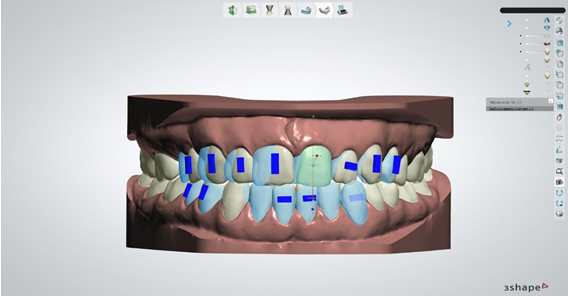

Slika 6. i 7.

Nakon odrađenih prethodno navedenih faza izrade modela I označavanja structure zuba, sustav ima dovoljno informacija da sam procijeni koja je granica anatomske krune zuba i na kojoj je poziciji gingivalni rub svake pojedine krune te isprekidanom linijom označava svaki pojedini zub. Ovdje moramo dobro iskontrolirati liniju koju je sustav označio I po potrebi je korigirati da linija obuhvaća zub u što je većoj mjeri moguće. Ako nismo zadovoljni sa onim što je algoritam odredio ili ćemo point editom ili free formom prepraviti rub te nakon toga stisnuti kalkulaciju. Nakon kalkulacije, sustav će segmetirati svaki pojedini zub I u digitalnom dizajnu ga razdvojiti na više manjih stl fileova koji predstavljaju svaki pojedini zub I bazu modela bez zuba

Slika 8. Ako smo zadovoljni sa segmentacijom zuba, obavezno proučavamo uputstva ortodonta koji bi nam morao dati točnu informaciju na kojim zubima i na kojim pozicijama želi da postavimo tzv. attachmente. Attachmenti su mali kompozitni oblici koji se apliciraju na zube koje je ortodont procijenio da su najoptimalniji za postavu attachmenta. Oni u kombinaciji sa udlagom znatno pospješuju pomake zuba te s njima možemo očekivati bolje, stabilnije I brže rezultate. Oblik attachmenta može biti raznoliki i također ovdje ortodont mora odabrati oblik attachmenta koji mu najviše odgovara. Također postoji i mogućnost dimplingsa koji umjesto attachmenta koji se lijepe na zub služe kao negativi u udlagi koji jače guraju zub u željenom smjeru.

Slika 9. Nakon svih odrađenih faza pristupamo zapravo najkraćoj fazi, a najbitnijoj, samoj prepostavi zuba koja u dizajnu vrlo sliči postavi zuba u mobilnoj protezi u fazi voska. Ono što je naš posao je dovesti zube u položaj koji je ortodont odredio u što je moguće precizniju poziciju poštujući iznose koje je ortodont odredio za pomake poput mezijalizacije, distalizacije, intruzije, ekstruzije, rotacije, angulacije, inklinacije itd. U to možemo biti sigurni jer nam za svaki pomak koji napravimo za pojedini zub sustav izbacuje sa strane iznose pomaka koje napravimo. Ako željena pozicija zuba prelazi vrijednosti koje je ortodont postavio onda je svakak potrebna dodatna konzultacija sa ortodontom da procjeni dali će ekscesivna vrijednost dovesti do neželjene recesije.